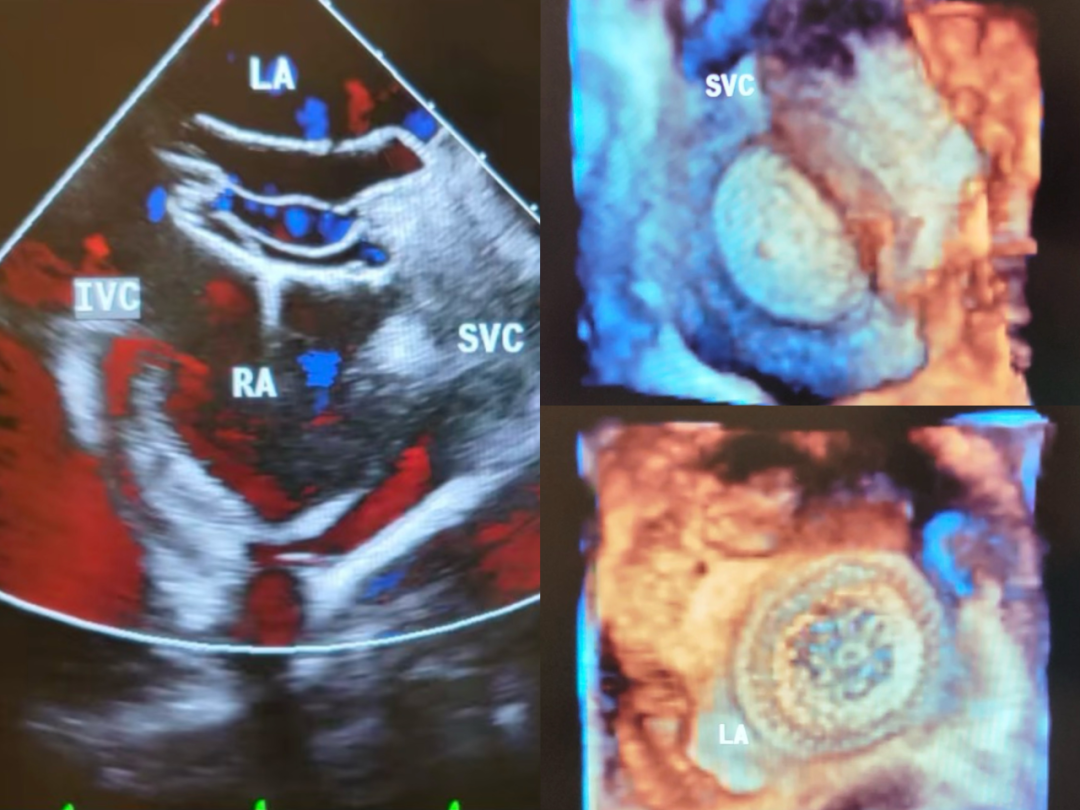

经食道超声心动图(TEE):为心脏手术及结构性心脏病介入治疗提供关键影像支持。

房间隔缺损封堵术中经食管超声心动图